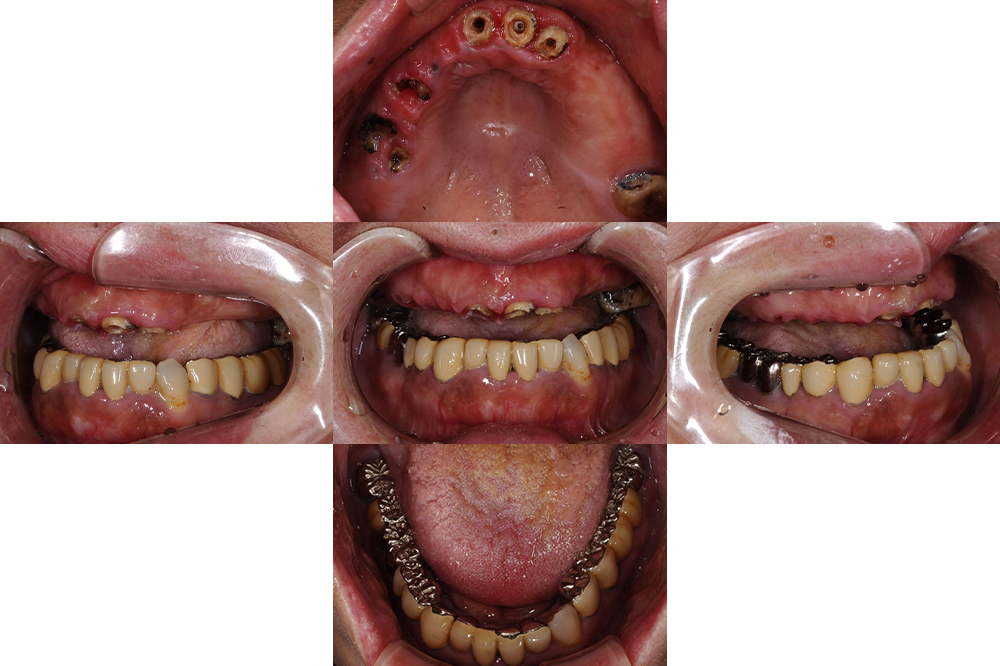

年齢 67歳 性別 女性 主訴/ニーズ 前歯がグラグラする 治療期間 1年 治療内容 ・インプラント ・セラミック修復 ・金属床義歯 費用 300万円 治療経過 上顎の残存歯が残念ながら虫歯で抜歯を余儀なくされ総義歯となった。 上顎の固定式も検討したがインプラントの…